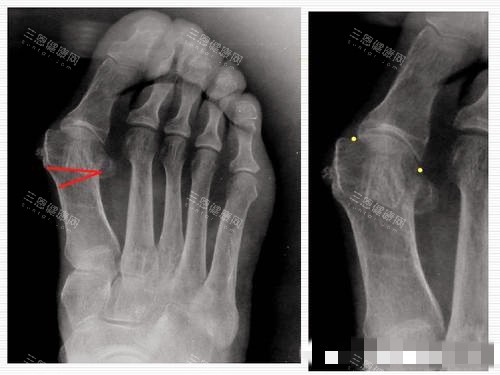

身边好多人受拇指外翻困扰 —— 穿鞋磨脚、走路疼,有的甚至影响运动和日常。

基本情况:拇指外翻 10 年,现在走路超过 1 小时就疼,脚趾还有点叠在一起,保守治疗没用

手术数据:手术 1 小时,住院 3 天,术后 10 天能慢走,4 个月修复正常,费用 2.5 万

亲身感受:术前怕修复慢,毕竟年纪不小了,苏医生说会用小创口技术,减少创伤。